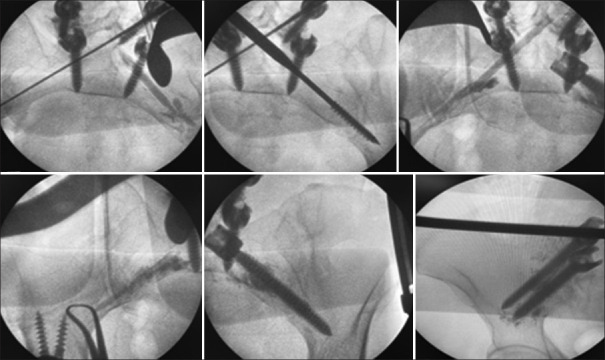

背景:聚甲基丙烯酸甲酯(PMMA)椎弓根螺钉增强术是一种用于降低机械并发症高风险患者椎弓根螺钉拔出、螺钉固定丢失和种植体失败风险的技术。研究设计:本研究为回顾性观察性研究。目的:本研究的目的是描述脊柱外科中传统椎弓根螺钉内固定的经典增强技术的改进。方法:回顾性分析47例65岁以上的脊柱手术患者,采用所建议的水泥增强技术,随访2年。将高粘度水泥注射到已攻丝的椎弓根内,然后置入传统椎弓根螺钉。患者的选择是基于详细的术前临床和影像学评估。测量的结果包括并发症的发生率,特别是水泥渗漏(CL),以及神经或血管缺损的发生率。结果:47例患者共使用700枚常规螺钉。700颗螺钉中有26颗(3.71%)出现CL。根据改进的Yeom分类,9/700(0.71%)为S型,9/700(0.71%)为B型,8/700(0.57%)为I型;没有神经或血管并发症。2年无机械并发症。结论:这种改良的椎弓根螺钉增强技术是老年患者脊柱内固定的一种替代方法,临床并发症发生率低,并且通过方便椎弓根螺钉置入减少了手术时间。

Methods: A retrospective analysis was performed on 47 patients over the age of 65 years who underwent spinal surgery using the proposed cement augmentation technique and were followed for 2 years. High-viscosity cement was injected into tapped vertebral pedicles, followed by the insertion of traditional pedicle screws. Patient selection was based on detailed preoperative clinical and imaging evaluations. Outcomes measured included the rate of complications, particularly cement leakage (CL), and the occurrence of neurological or vascular deficits.